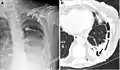

Extensive left-sided fibrothorax

Chest radiograph displaying inhomogeneous opacification of the left half of the chest that is fibrothorax

A fibrothorax can typically be diagnosed by taking an appropriate medical history in combination with the use of appropriate imaging techniques such as a plain chest X-ray or CT scan.[3] These imaging techniques can detect fibrothorax and pleural thickening that surround the lungs.[7] The presence of a thickened peel with or without calcification are common features of fibrothorax when imaged.[3] CT scans can more readily differentiate whether pleural thickening is due to extra fat deposition or true pleural thickening than X-rays.[3]

If a fibrothorax is severe, the thickening may restrict the lung on the affected side causing a loss of lung volume.[7] Additionally, the mediastinum may be physically shifted toward the affected side.[3] A reduction in the size of one side of the chest (hemithorax) on an X-ray or CT scan of the chest suggests chronic scarring.[6] Signs of the underlying disease causing the fibrothorax are also occasionally seen on the X-ray.[6] A CT scan may show features similar to those seen on a plain X-ray.[7] Lung function testing typically demonstrates findings consistent with restrictive lung disease.[6]